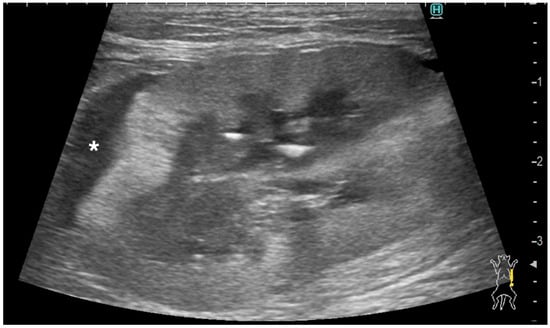

| Case | Signalment | Affected Kidney | US Findings of Subcapsular Thickening Lesion | US Findings of the Kidney | Diagnosis of Renal Lesion | Diagnosis of Other Organs | |||||||||||||

|---|---|---|---|---|---|---|---|---|---|---|---|---|---|---|---|---|---|---|---|

| Distribution | Maximum Thickness (mm) | Echotexture | Echogenicity | Renal Cortical Margin | Renal Capsular Margin | Vascularity | Perirenal Effusion | Architecture | Characteristic Pattern | Corticomedullary Distinction | Renal Pelvis Diameter (mm) | Mineralization | Cystic Lesion | Nodule | |||||

| 1 | 10 year-old, MN, DSH | left | focal | 3.5 | homo | hypo | irregular | irregular | no | no | normal | ill-defined | 1.3 | no | no | yes | Metastatic Carcinoma and Suspected Metastatic Carcinoma (sample obtained from either right or left kidney) | Pulmonary Carcinoma (lung, muscle) | |

| right | focal | 3.5 | homo | hypo | irregular | irregular | no | no | abnormal | hypoechoic striations within hyperechoic areas | ill-defined | no dilation | no | no | no | ||||

| 2 | 15 year-old, FN, DSH | left | focal | 1 | homo | hypo | smooth | smooth | NA | no | abnormal | ill-defined | no dilation | no | no | no | Suspected Metastatic Carcinoma | Pulmonary Carcinoma (lung, muscle) | |

| 3 | 11 year-old, MN, DSH | right | focal | 2.8 | homo | hypo | irregular | smooth | yes | no | abnormal | ill-defined | no dilation | no | no | yes | Suspected Metastatic Carcinoma | Pulmonary Carcinoma (lung) | |

| 4 | 9 year-old, FN, DSH | left | focal | 4.8 | homo | hypo | irregular | irregular | no | no | abnormal | hypoechoic striations within hyperechoic areas | ill-defined | no dilation | no | no | no | Metastatic Carcinoma | Pulmonary Carcinoma (lung) |

| right | focal | 1.5 | homo | hypo | smooth | smooth | NA | no | abnormal | well-defined | no dilation | no | no | no | Suspected Metastatic Carcinoma | ||||

| 5 | 14 year-old, FN, DSH | left | focal | 1.2 | homo | hypo | smooth | smooth | NA | no | abnormal | hypoechoic striations within hyperechoic areas | ill-defined | no dilation | no | no | no | Metastatic Carcinoma | Pulmonary Carcinoma (lung) |

| 6 | 11 year-old, MN, DSH | left | focal | 3 | homo | hypo | smooth | smooth | NA | yes | normal | ill-defined | no dilation | yes | no | no | Metastatic Carcinoma | Metastatic Carcinoma (lung) | |

| right | circumferential | 13.2 | hetero | hetero | irregular | irregular | yes | yes | abnormal | completely effaced | 1.9 | yes | yes | no | Primary Renal Carcinoma | ||||